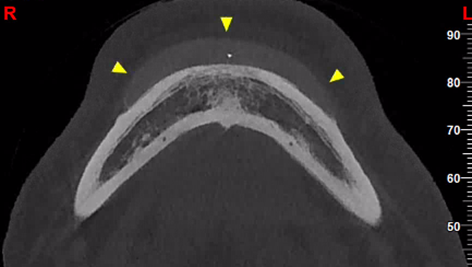

Απεικονιστικά παρατηρούνται πολλαπλές συρρέουσες υπέρπυκνες δομές μικρών διαστάσεων εντός των μαλακών μορίων και πλησίον του εξωτερικού τους περιγράμματος.

Συνήθης εντόπιση: